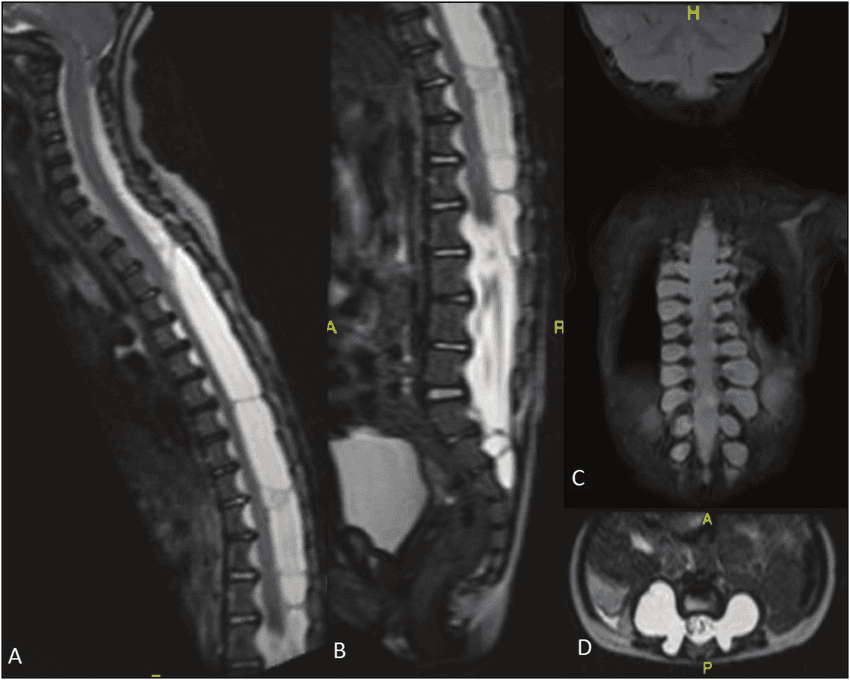

Relata-se o caso de um paciente masculino de 27 anos portador de neurofibromatose tipo 1 (NF1), apresentando escoliose distrófica severa, hemivértebra, múltiplos neurofibromas plexiformes e nodulares, e ectasia dural. Os exames de ressonância magnética evidenciaram deformidades vertebrais acentuadas, rigidez angular e remodelamento das paredes posteriores. A espirometria demonstrou distúrbio ventilatório obstrutivo moderado com redução da capacidade vital, indicando comprometimento funcional. O caso evidencia a interação entre predisposição genética, deformidade estrutural, carga tumoral e deterioração neuromuscular progressiva, reforçando a necessidade de abordagem multidisciplinar e a complexidade das contraindicações cirúrgicas na NF1 avançada.

Os exames de imagem revelaram escoliose torácica grave (>80° estimado), com deformidade rotacional e fusão parcial dos corpos vertebrais, compatíveis com morfologia distrófica [2]. Observou-se ectasia dural lombossacra com remodelamento posterior em L5–S2 e múltiplos neurofibromas plexiformes e nodulares em trajetos paravertebrais e lombossacrais, compatíveis com infiltração tumoral difusa.

O caso ilustra a complexidade fisiopatológica da NF1 com escoliose distrófica grave, hemivértebra, ectasia dural e múltiplos neurofibromas plexiformes. A repercussão respiratória e motora observada confirma a gravidade e o prognóstico reservado. A RM, especialmente com protocolos 3D T2 isotrópicos, DWI e pós-contraste, permanece essencial para diagnóstico e monitoramento. Diretrizes atuais recomendam vigilância seriada por RM segmentar e WBMRI em intervalos de 2 a 3 anos [3].